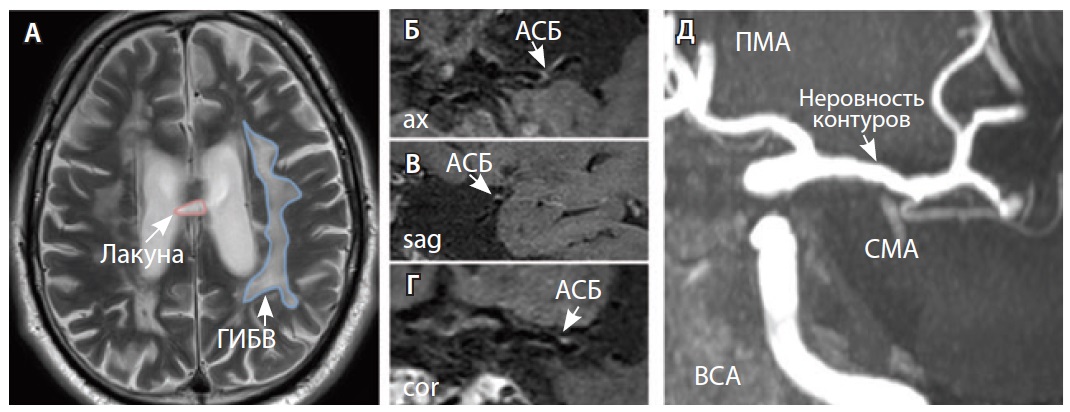

Рис. 3. Пациент Ц., 53 года, с признаками церебральной микроангиопатии (F3 по шкале Fazekas), атеросклерозом интракраниальных артерий, без формирования гемодинамически значимых стенозов. А – магнитно-резонансная томография (МРТ) головного мозга, режим Т2-взвешенного изображения: видны обширные сливные зоны гиперинтенсивности белого вещества (ГИБВ) с наличием на этом фоне лакунарных инфарктов; Б, В, Г – МРТ сосудистой стенки, режим T1-TSE-db-FS после контрастного усиления: в сегменте М1 левой средней мозговой артерии (СМА) визуализируется эксцентричная атеросклеротическая бляшка (АСБ), интенсивно накапливающая контрастный препарат; Д – трехмерная магнитно-резонансная времяпролетная (3D ToF) ангиография: выявляется неровность контуров левой СМА в сегменте М1; ax – аксиальная, sag – сагиттальная, cor – коронарная плоскости; ВСА – внутренняя сонная артерия; ПМА – передняя мозговая артерия

Рис. 4. Пациент К., 69 лет, с признаками церебральной микроангиопатии (F2 по шкале Fazekas) и атеросклерозом интракраниальных артерий, с формированием гемодинамически значимого стеноза в сегменте М1 правой средней мозговой артерии (СМА): А – магнитно-резонансная томография (МРТ), режим Т2-взвешенного изображения: видны множественные сливные очаги гиперинтенсивности белого вещества (ГИБВ); Б, В – МРТ сосудистой стенки, режим T1-TSE-db-FS после контрастного усиления: в сегменте М1 правой СМА визуализируется эксцентричная атеросклеротическая бляшка (АСБ), интенсивно накапливающая контрастный препарат; Г – трехмерная магнитно-резонансная времяпролетная (3D ToF) ангиография: виден стеноз правой СМА в сегменте М1; Д – режим HR Т2-TSE: видна АСБ в сегменте М1 правой СМА; ax – аксиальная, sag – сагиттальная плоскости; ЗМА – задняя мозговая артерия; ПМА – передняя мозговая артерия